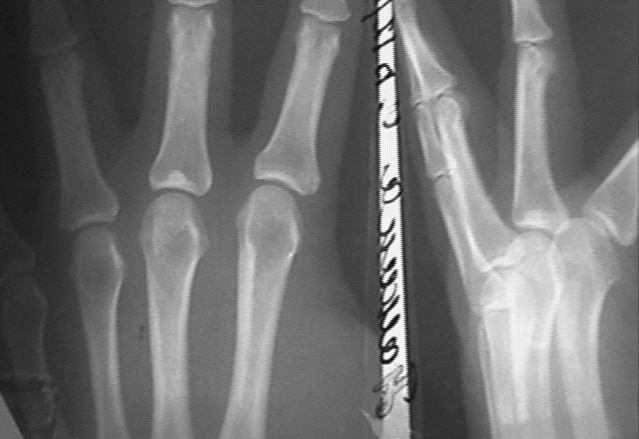

У больной П 30 лет появились боли 3 месяца назад в области пальца. В течении последнего месяца появилось образование. При осмотре на ладонной поверхности 3 го пальца на уровне межпальцевой складки пальпируется образование 03*04 см плотное болезненное. Сделана рентгенограмма. Мной расценено, что у больной имеется два заболевания: 1) Фиброма пальца 2) Остеома? основания основной фаланги случайно найденная. Планируется иссечение фибромы с гистологическим исследованием. Повторное рентгенологическое исследование через год. Уважаемые коллеги, как по вашему мнению поступить с костным образованием фаланги?Сергей Зырянов ЦРБ Новосибирская область г Куйбышев

Уважаемый колега! Думаю, что с остеомой затягивать не следует. По нашему мнению необходимо произвести ее иссечение тыльным доступом через "окончатую" остеотомию с последующей аутопластикой дефекта костным трансплантатом.